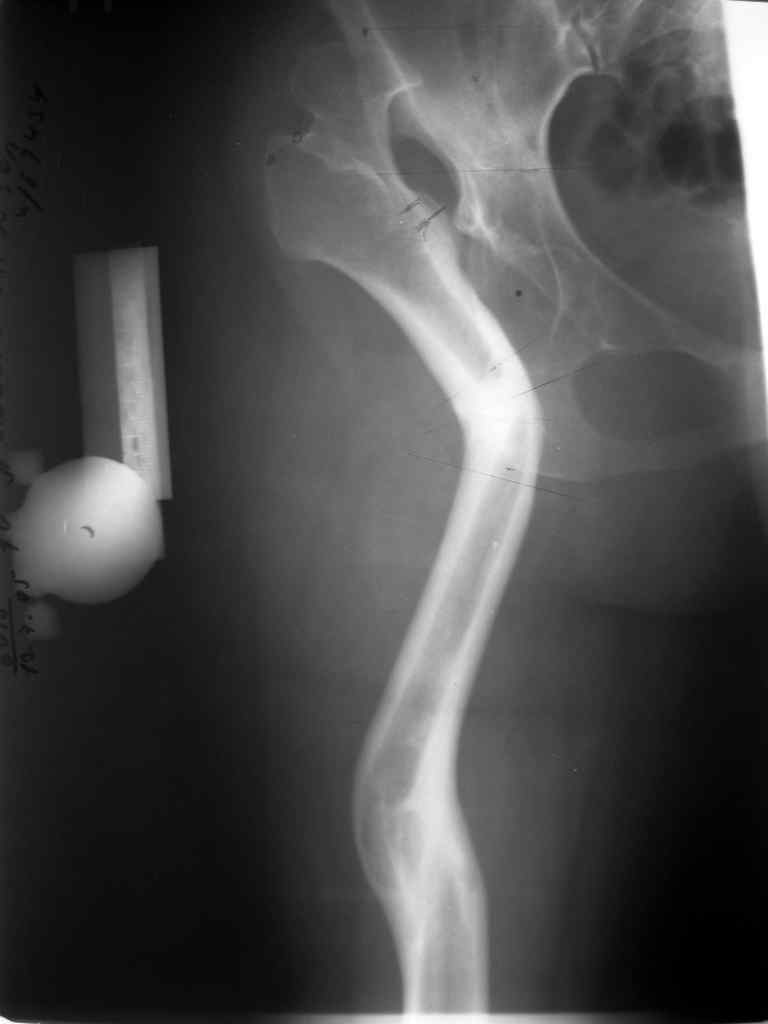

Поднят очень интересный вопрос об эффективности создания опорного бедра по Илизарову у молодых пациентов (ок). Наверное мне не повезло и я не

видел положительных результатов после этих операций, а вот проблемных больных приходится видеть достаточно часто. Причем сроки их обращения

после остеотомии короткие - 3-5 лет, а выполнение эндопротезирования после остеотомии на двух уровнях с многоплоскостной деформацией является

остеотомии. Я представил Р-граммы больных с неудачными р-ми после остеотомий.

Эндопротезирование у них было на порядок сложнее в отличие от артропластики без проведения остеотомии.